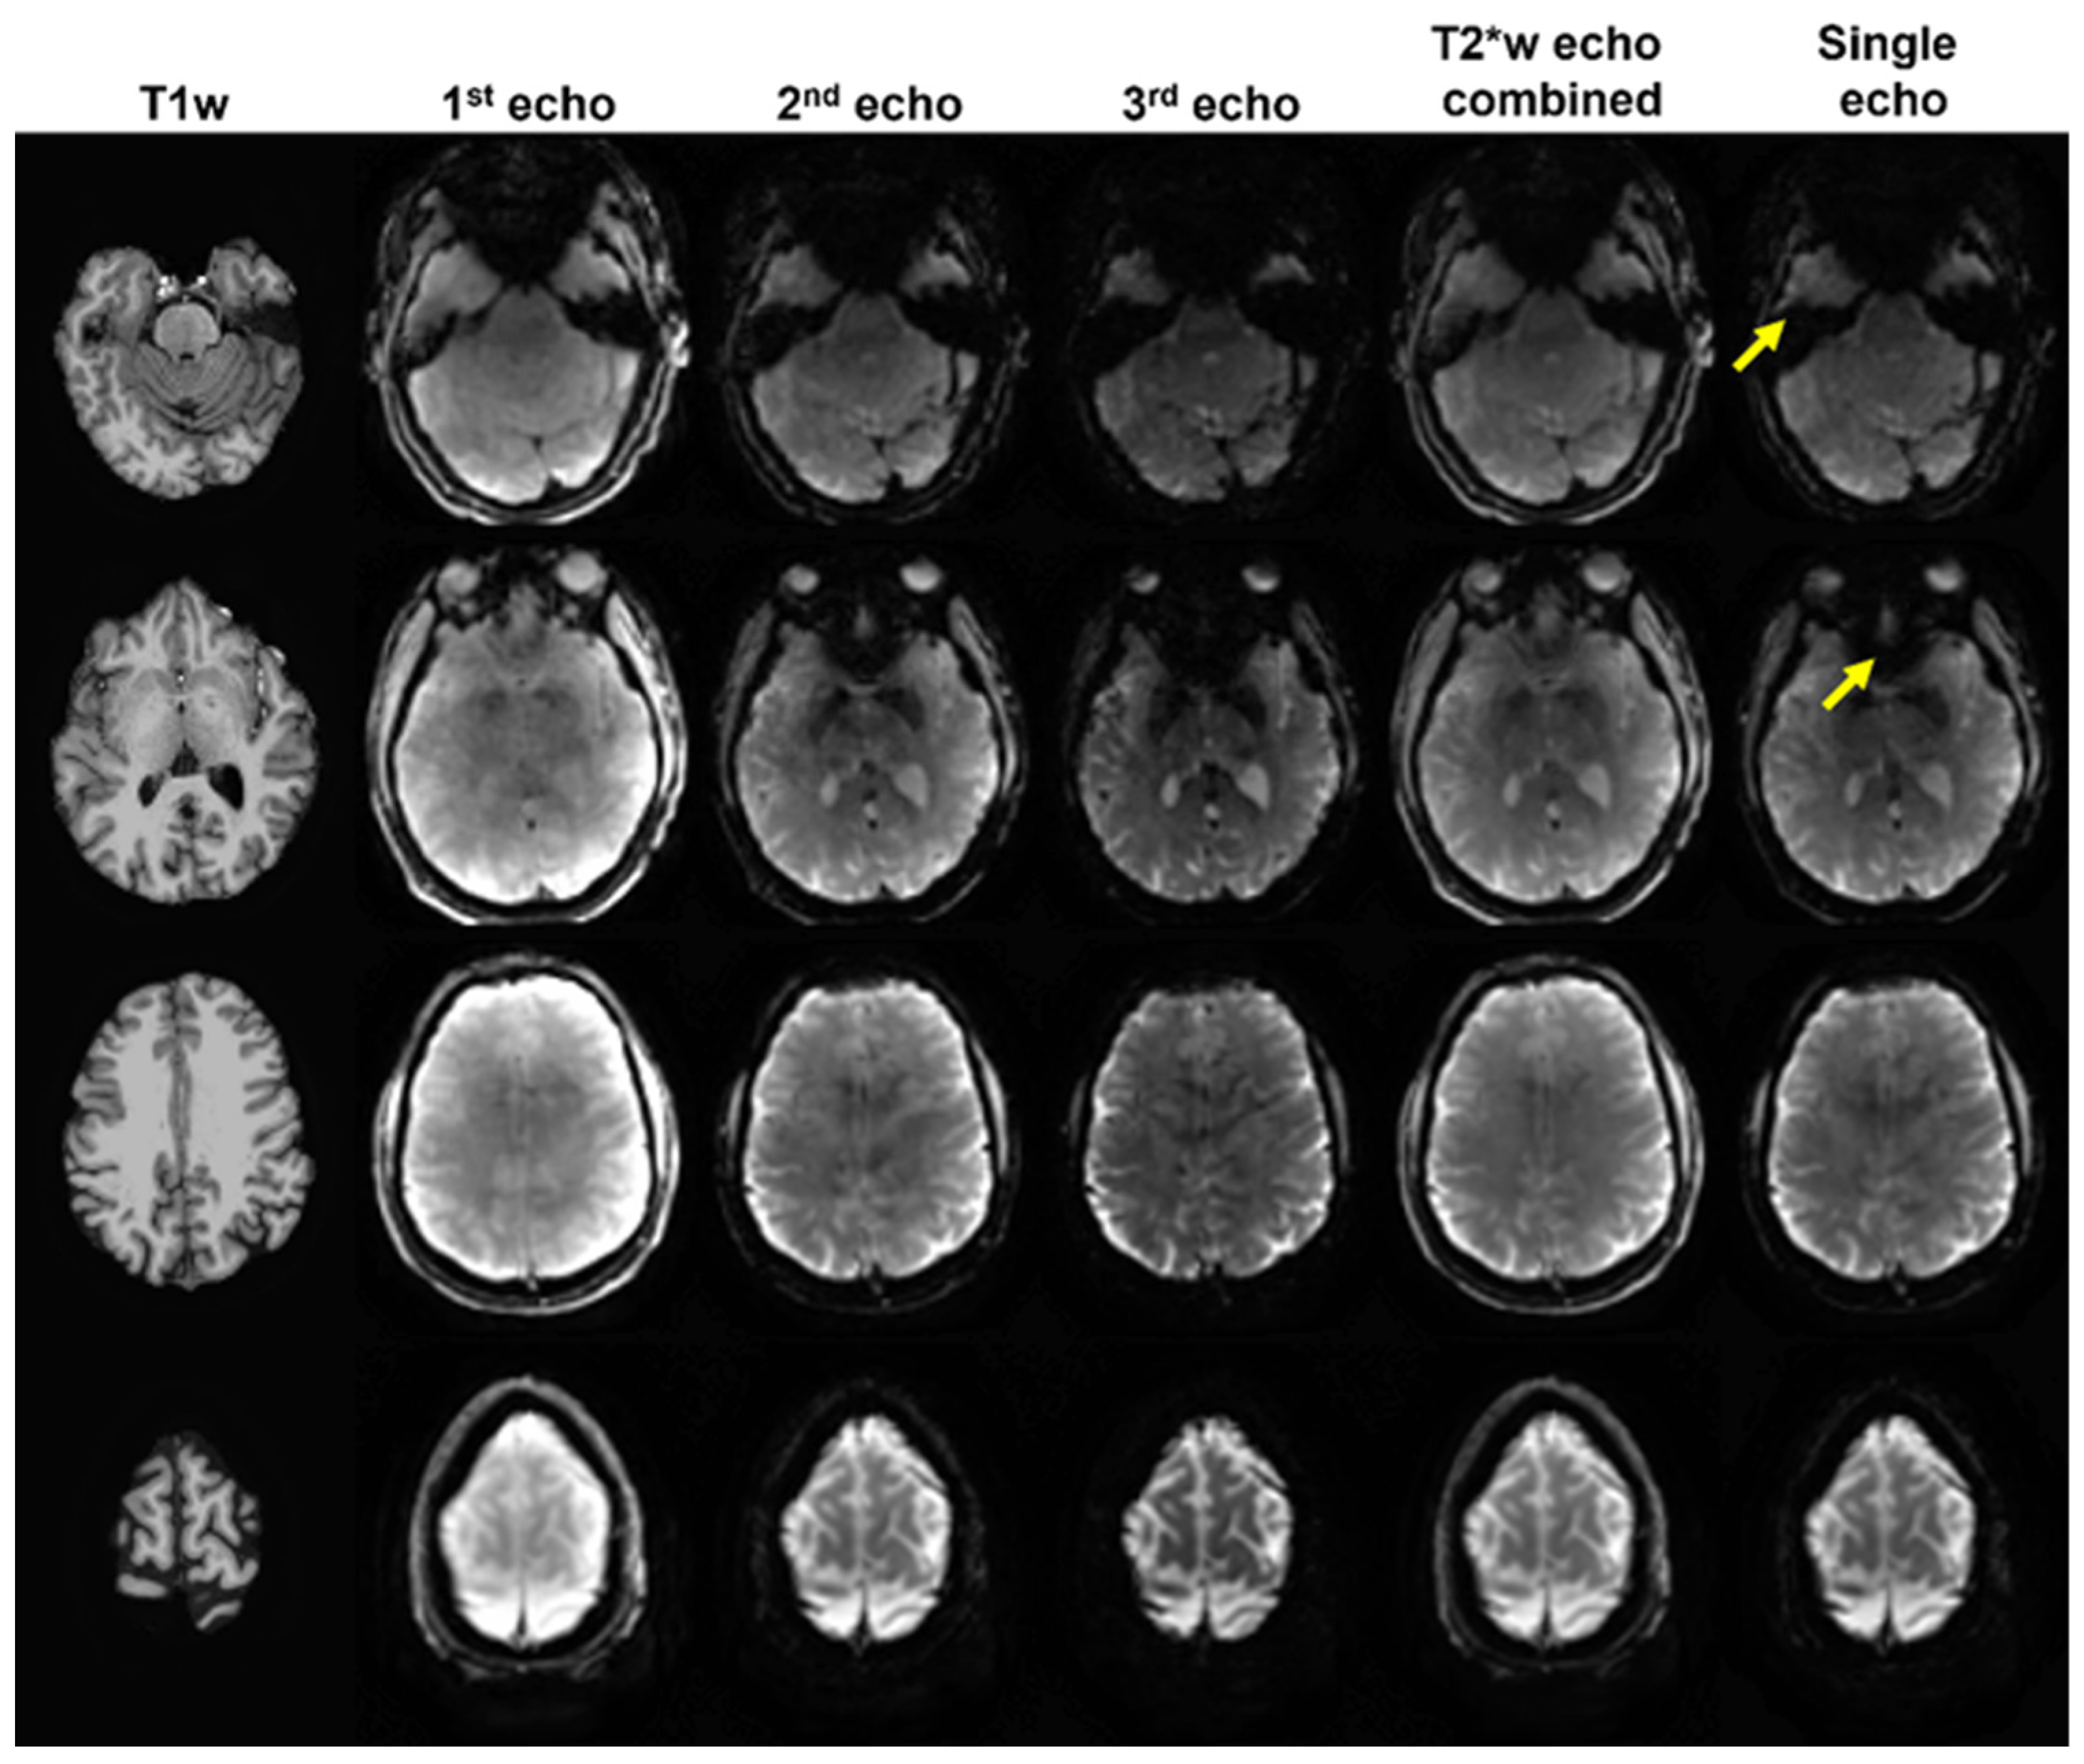

3.1. Data Selection for Analysis